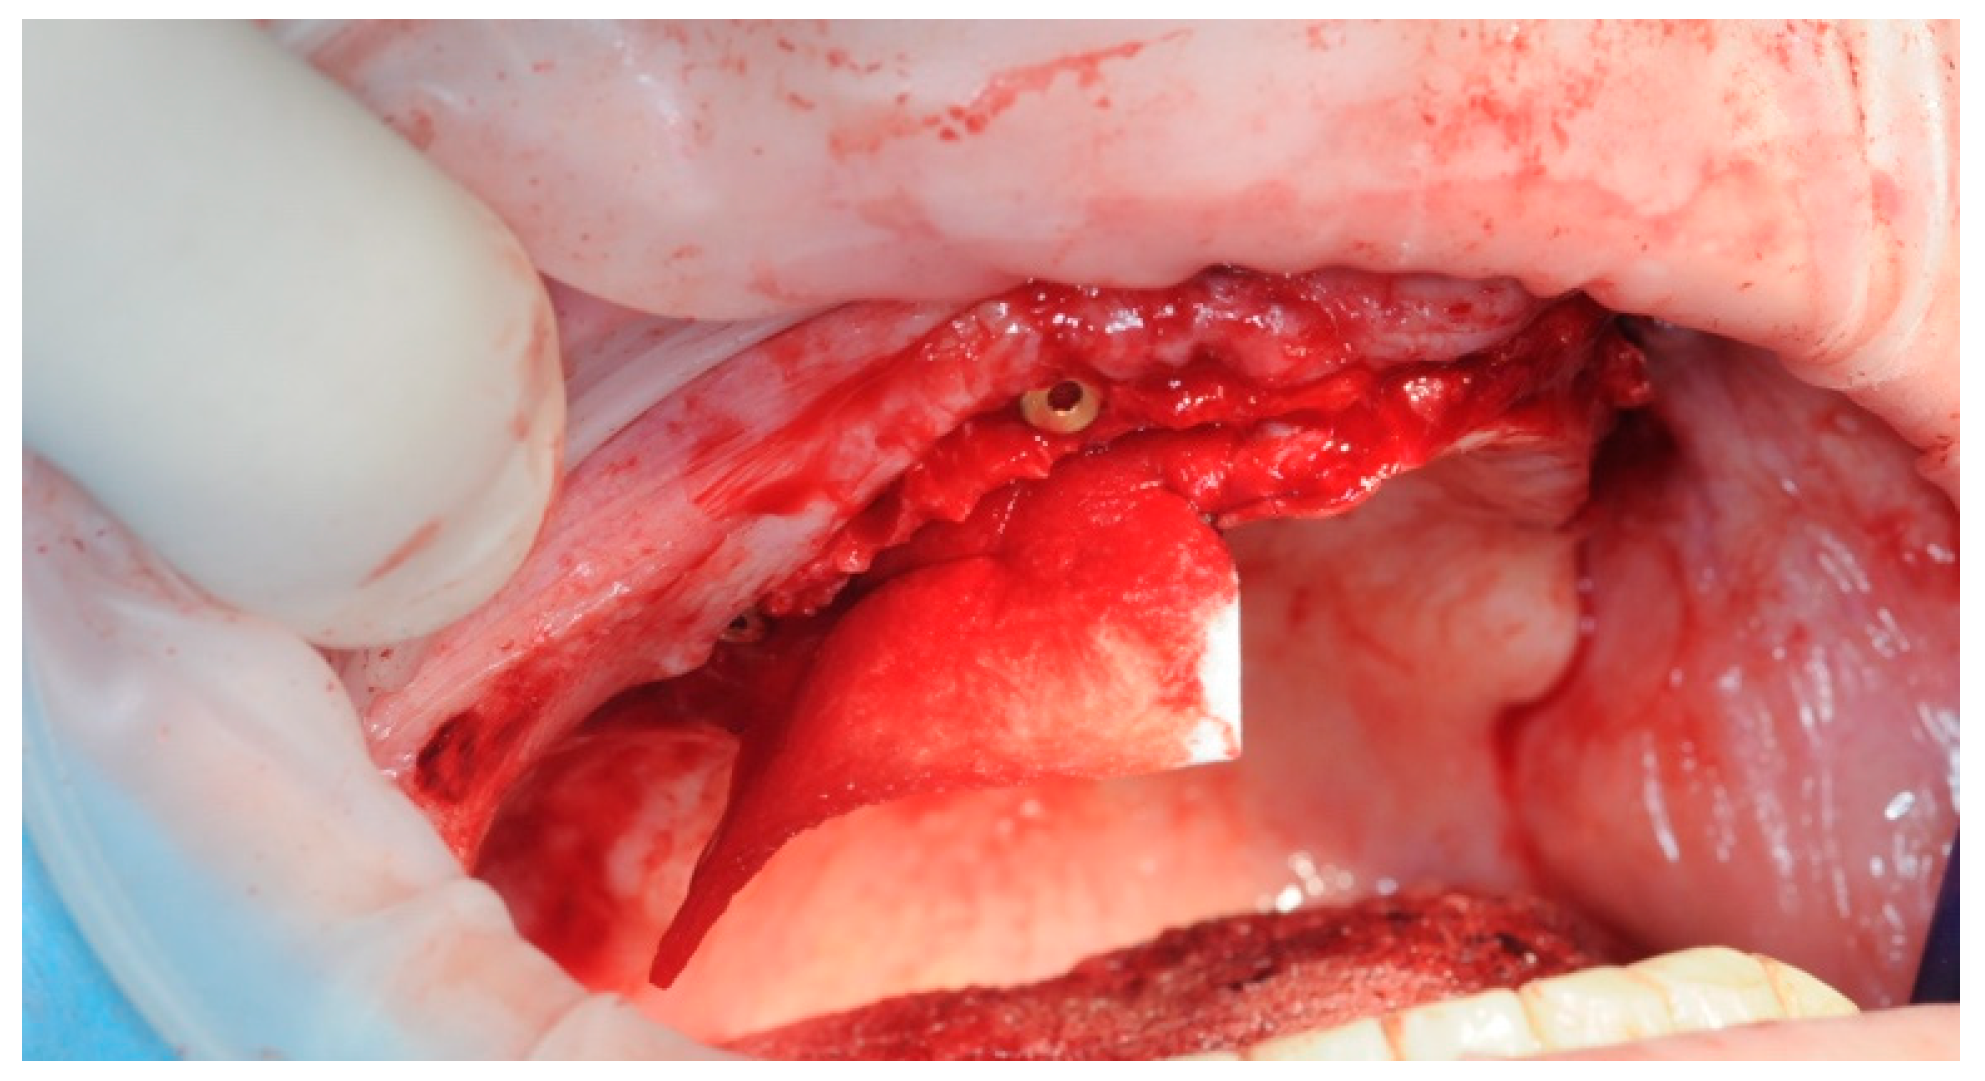

2.3. Re-Entry Surgery

3.4. Soft Tissue Management